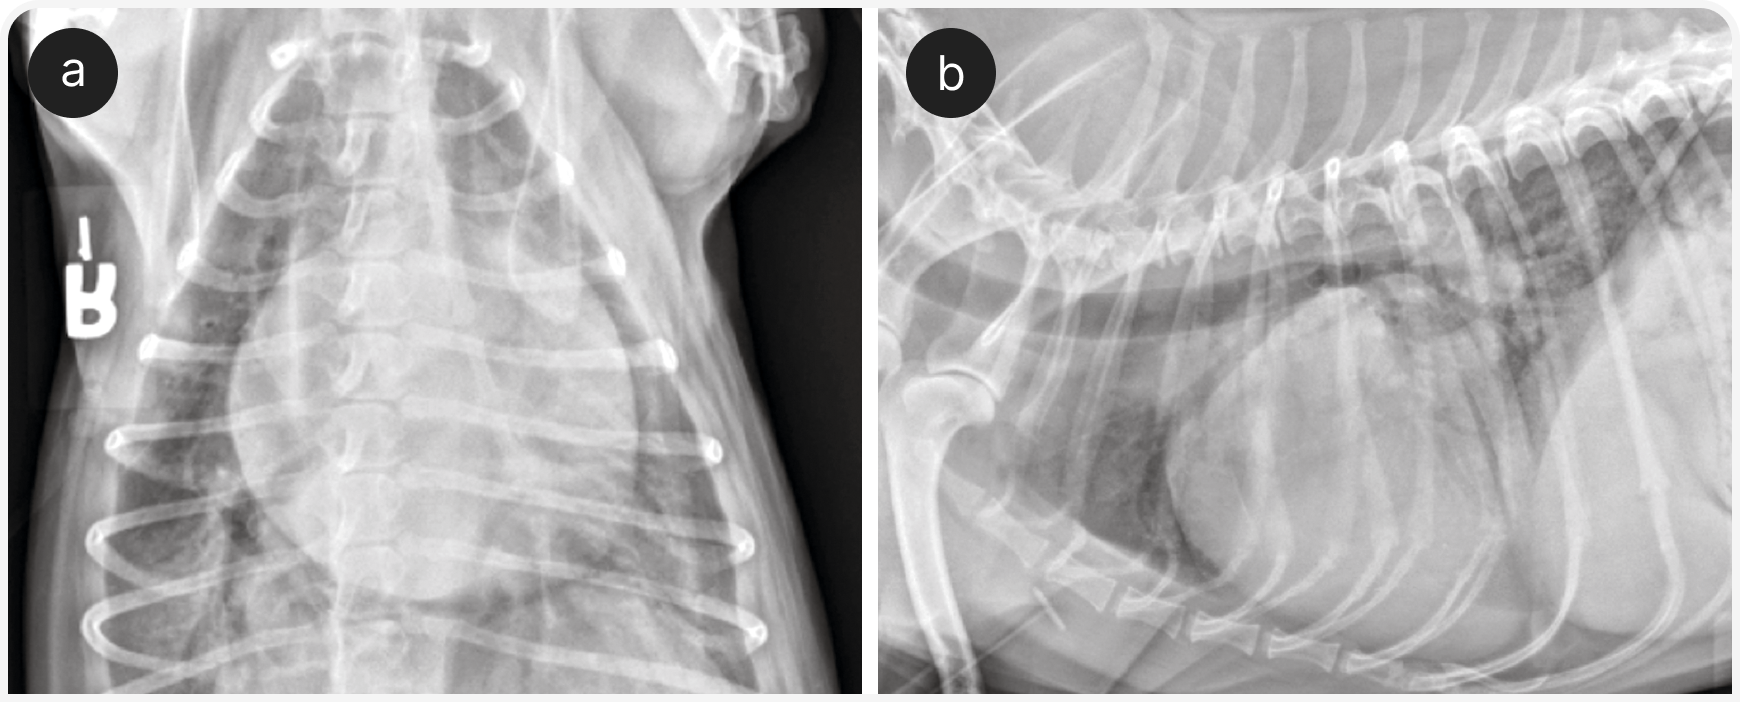

Для диагностики гемоторакса, транссудата в сравнении с экссудатом или септического выпота рекомендуется определить гематокрит, общее содержание растворенных веществ в плазме крови, содержание глюкозы, лактата, а также провести экспресс-цитологическое исследование выпота. После торакоцентеза показана рентгенография органов грудной клетки для выявления легочной буллы, объемного образования в легких, кардиомегалии или другой причины (Рисунки 6 и 7).

В ожидании результатов первоначального обследования также может быть показана компьютерная томография. Если пациенту требуется несколько торакоцентезов, безусловно, следует рассмотреть возможность установить торакостомическую трубку до проведения дальнейшей диагностики и/или до окончательного лечения (например, операции по поводу спонтанного пневмоторакса вследствие буллы).

В этих случаях также возможно поражение легких и/или плевральной полости (например, ушибы легких или пневмоторакс), поэтому аускультативная картина изменчива; для выявления некоторых из этих изменений (например, плеврального выпота, отека легких или отсутствия признака скольжения) может быть полезен POCUS. Если проникающее поражение грудной стенки не очевидно сразу, для выявления его симптомов целесообразно провести рентгенографию органов грудной клетки, поскольку его требуется лечить хирургически (Рисунок 8).

Хирург должен осмотреть все наружные раны и, независимо от результатов визуализации, подготовиться к исследованию грудной полости. Это связано с тем, что по наружной ране часто не удается полностью оценить всю степень повреждения.